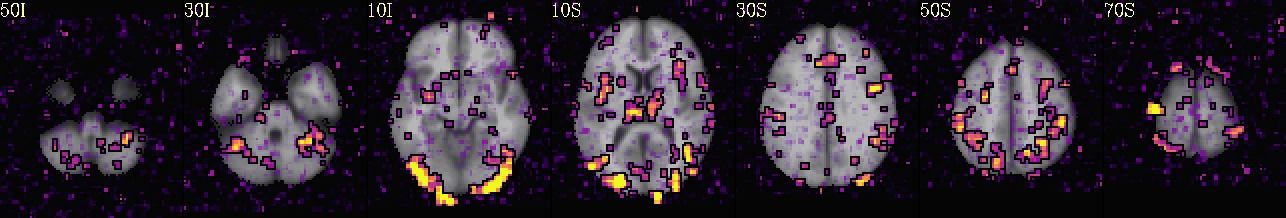

Running Preprocessing and First Level Analysis for sub-08#

All of the preprocessing steps (from setup through scaling) for subject sub-08 were introduced and explained in the example notebook about Preprocessing with AFNI- which is highly inspired by Andy’s Brain Book’s excellent AFNI tutorial. There, it is covered how to use afni_proc.py to generate an automated pipeline, and how to interpret each preprocessing block. In this section, we extend that workflow by adding a regress block to model task-related brain activity using a general linear model (GLM):

Preprocessing and GLM Workflow:

➡️ setup ➡️ tcat ➡️ align ➡️ tlrc ➡️ volreg ➡️ blur ➡️ mask ➡️ scale ➡️ regress 🧠

outputs: includes fitted time series, beta weights, and statistical maps from the GLM.

🧾 regress step: Incorporates timing files, HRF modeling (GAM), symbolic GLTs, and executes 3dREMLfit for improved autocorrelation modeling.